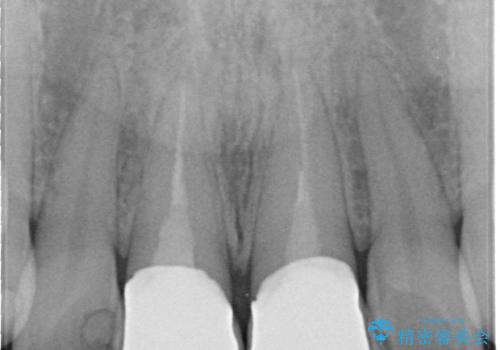

かぶせ物と歯の境目の再設定を行い、適合の良いかぶせ物を装着することで、審美的に自然な状態に改善することができました。